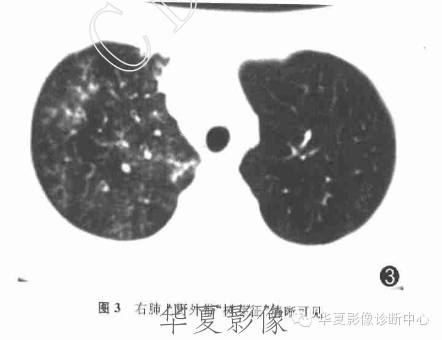

支原体肺炎1例CT影像表现